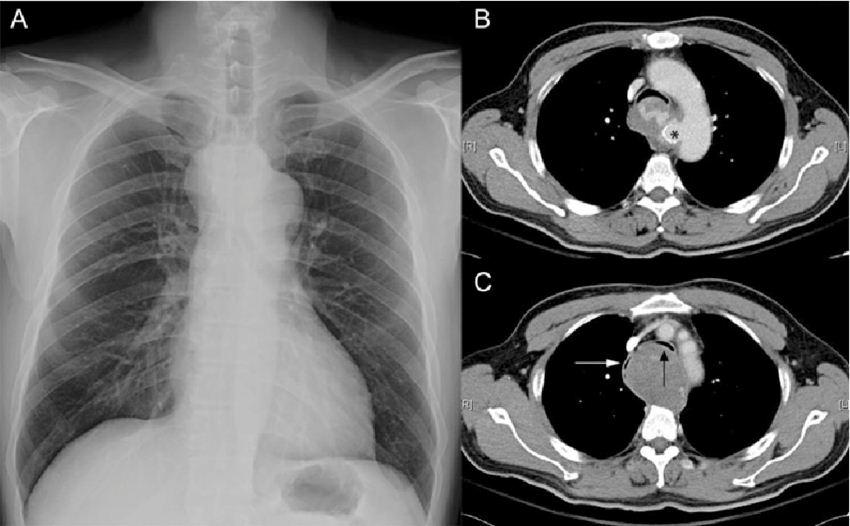

CT scan dada merupakan pemeriksaan CT scan yang dilakukan untuk mendapatkan informasi tentang organ-organ dan struktur di dalam dada yang lebih mendetail dibandingkan foto rontgen dada biasa.

Dada terdiri dari organ-organ pernapasan, sistem kardiovaskular, dan juga esofagus (saluran yang menghubungkan rongga mulut ke lambung). CT scan dada bisa dilakukan untuk melihat dada dan organ-organ di dalamnya, misalnya untuk:

1. mengetahui apakah terdapat tumor, cedera, perdarahan, infeksi, sumbatan, atau kondisi lainnya, terutama jika gangguan tidak jelas terlihat dengan pemeriksaan rontgen dada biasa.

2. mengetahui letak tumor, terutama tumor yang menyumbat bronkus

3. mengevaluasi ukuran, bentuk, dan posisi organ-organ di dada dan perut bagian atas

4. melihat adanya perdarahan atau akumulasi cairan di paru-paru atau daerah lainnya

5. mengevaluasi efek terapi tumor di dada

6. panduan untuk melakukan tindakan medis tertentu, misalnya memandu penusukan jarum untuk biopsi tumor di dalam dada atau untuk aspirasi cairan dari dalam dada